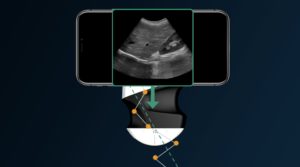

The system comprised of two ultrasound probes (one convex, one linear) , each with rechargeable batteries, and an i-pad. The probes sent information to the i-pad using their own wi-fi system, so they could be used absolutely anywhere.